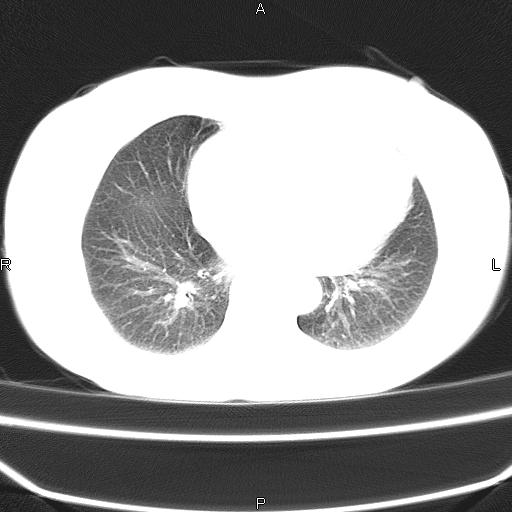

患者,女,66岁。健康体检胸部透视发现右上肺片状阴影。既往无不适,患者自诉三个月前曾有低热病史体温37.5左右一周。用药后缓解。至今无其它不适。请老师们指导指导。

考虑:右肺上叶周围型肺癌(分叶状肿块+砂粒状钙化+胸膜尾征)。

病灶见明显分叶、大小较大(大于3cm?),老年人,多考虑:肺癌,建议穿刺活检。

典型的中心型肺癌,尖段支气管阻塞。

以下是引用dyqct在2010-6-3 9:32:00的发言:[br]考虑:右肺上叶周围型肺癌(分叶状肿块+砂粒状钙化+胸膜尾征)。

不像中央型啊

周围性肺癌,

周围性肺癌可能性大,建议增强

右肺上叶周围型肺癌可能性大。

考虑:右肺上叶周围型肺癌